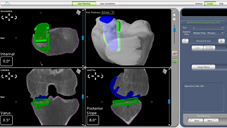

相較以往傳統人工膝關節置換手術其工程浩大,除了要切除所有關節面,也必須切除2條十字韌帶,但有些患者,只有1/2到1/3的關節面壞掉須置換,而且十字韌帶還健康並未老化鬆弛。若是這些患者的關節面全部切除,其實有點可惜。因此,藉由機器人手臂協助置換人工膝關節的方式,可幫助上述的患者保留仍是健康的軟骨和韌帶。機器人手臂手術在術前也會做病人膝部3D電腦斷層掃瞄,重建骨骼模型,以提供術前計畫及術中執行所需。醫師在手術進行中可與機器人手臂的電腦模擬做視覺及觸覺互動,只磨掉有病變的軟骨,一旦超過術前設定範圍時會自動停止,避免其組織受到傷害。利用機器人手術不但能降低手術誤差,更可以保好骨質,術後恢復期也能大幅降低至3天以內,是膝關節退化性關節炎患者的另一項新選擇。

機器人手臂設備

術前三維電腦斷層掃描輸入機器人手臂,以供術前計畫及術中執行所需。

磨掉有病變的軟骨